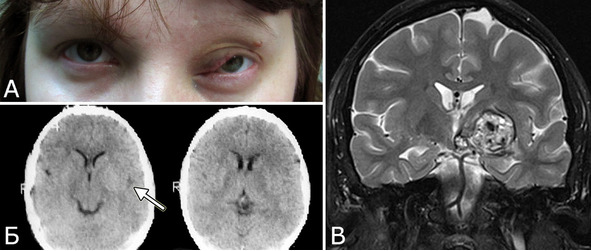

Рис. 26. Б-ная В-ва, 1982 г. р. Радиоиндуцированная (?) кавернозная мальформация. Амбулаторное обследование в НХИ в 2011 г (29 лет). А – внешний вид больной, 2011 г. Б – КТ головы, 1995г. В – МРТ головы, 2011 г (режим Т2, фронтальная проекция). Клинический диагноз: Врожденная капиллярная гемангиома левой половины лица и орбиты. Кавернозная мальформация базальных ганглиев, зрительного бугра и ножки мозга слева. Клиническое течение и лечение: с рождения – увеличение и деформация мягких тканей левой половины лица. Наблюдалась в НИИ глазных б-ней им. Гельмгольца с диагнозом «капиллярная гемангиома лица и орбиты». Проведено 5 курсов рентгенотерапии, курс радиотерапии. В 13-летнем возрасте (1995 г) выполнена коагуляция сосудов орбиты. При КТ головы в НИИ нейрохирургии патологии не обнаружено. В 2011 г (29 лет) постепенно развился правосторонний гемипарез, правосторонняя гемигипестезия. Обратилась в институт. При обследовании: глубокий правосторонний пирамидный гемипарез, гемигипестезия, гомонимная гемигипопсия. При МРТ выявлена типичная крупная кавернома базальных ганглиев справа (В). При ретроспективном рассмотрении КТ 1995 г (Б) можно предполагать наличие практически изоплотностного по отношению к ткани мозга округлого образования базальных ганглиев слева (стрелка), совпадающее по локализации с КМ, выявленной в 2011 г.